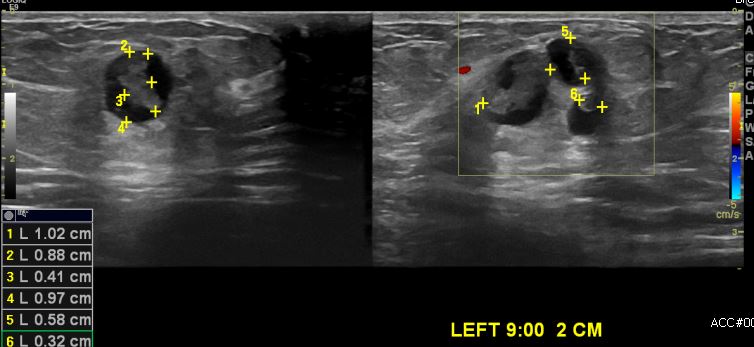

건강검진상 이상 소견으로 내원하신 60대 여성 분으로 좌측 9시 방향의 의심스러운 혹

조직검사 시행하여 좌측 유관암 진단 되었습니다.